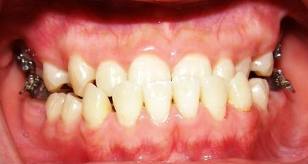

Bên cạnh hàm vẩu, móm mém (loại khớp cắn ngược) là một thể khiếm khuyết răng hàm mặt hay gặp ở ngườiViệt Nam. Thể hiện sự móm rất dễ dàng nhận biết: xương hàm dưới bị đưa ra phía trước, khi ngậm miệng răng hàm dưới ôm phủ ngoài răng hàm trên, cằm bị lệch, gây mất hài hòa cho khuôn mặt bị kém thẩm mỹ. Ngoài ra còn thêm các khó khăn khi ăn nhai…

Móm (khớp cắn ngược) do răng:

Móm dạng này vấn đề chính nằm ở vùng răng cửa giữa. Cách thức xử lý khá đơn giản. Tuy nhiên khi không được điều trị sớm và chỉnh sửa kịp thời thì phần răng và xương hàm trên sẽ bị ảnh hưởng. Điều này gây nên sự kém phát triển của hàm trên, làm gương mặt góc nghiêng bị gãy, nhìn mất độ thẩm mỹ.